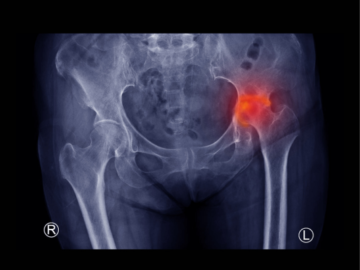

歩くと股関節が痛くなり、整形外科を受診すると

レントゲンやCT、MRIなどの検査を行い、

変形性股関節症

股関節唇損傷

臼蓋形成不全(発育性股関節形成不全)

といった診断名を告げられるケースは少なくありません。